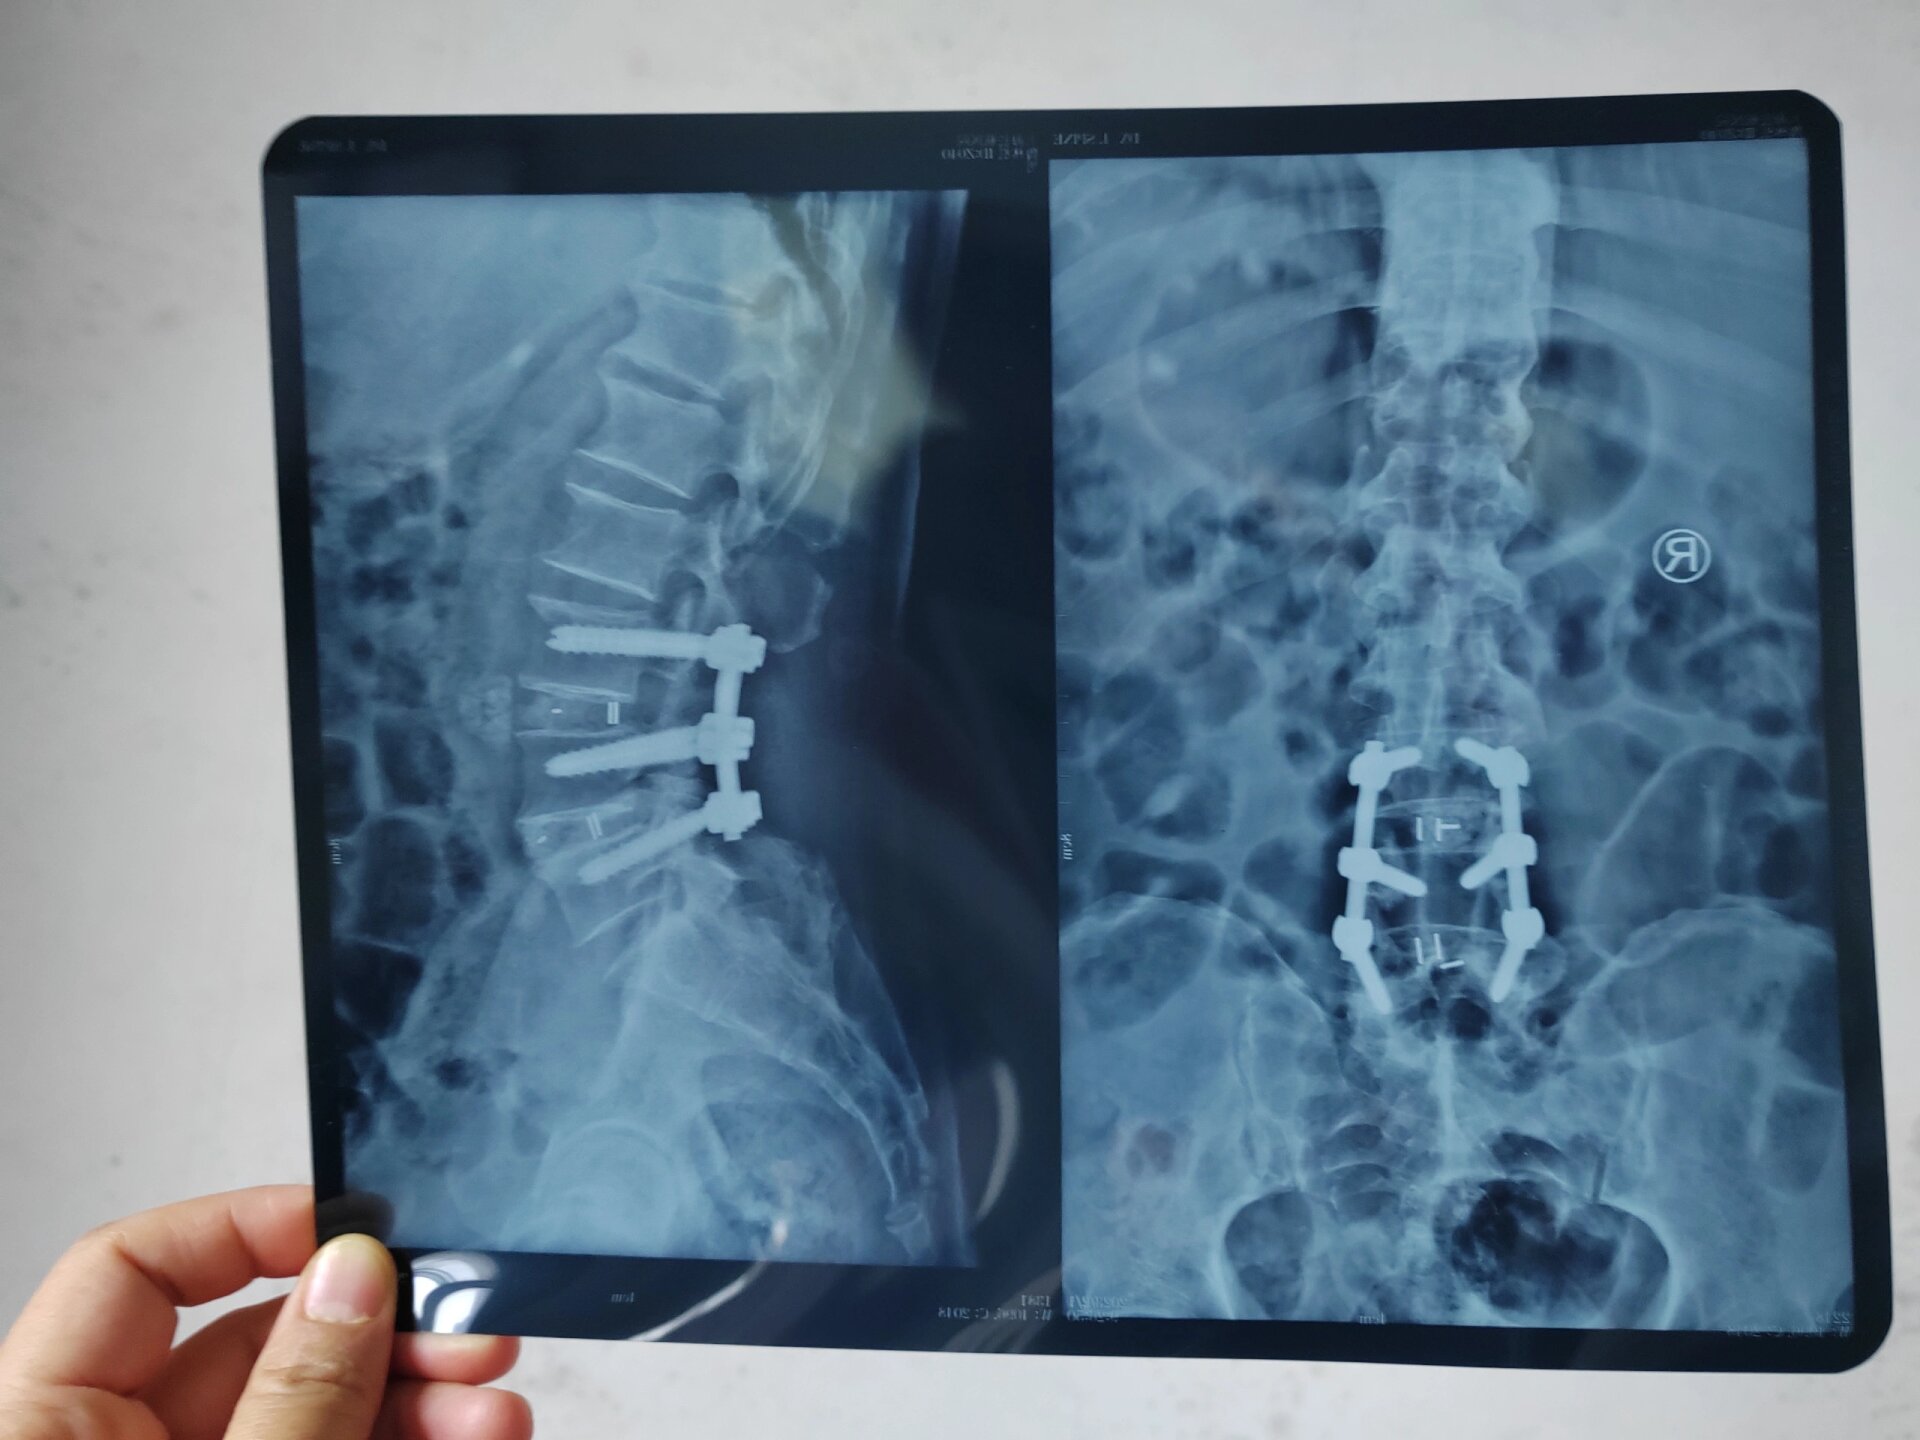

腰椎开放融合术6个钢钉